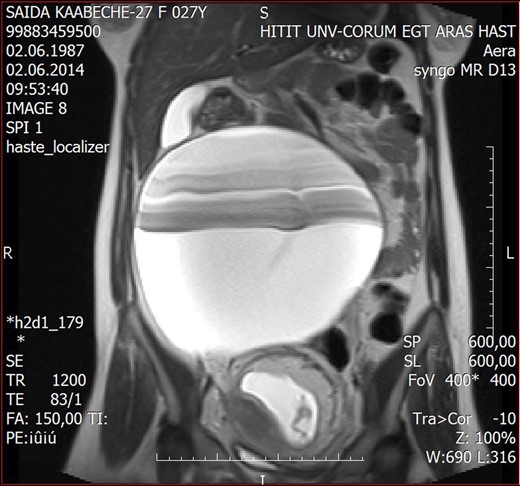

To arrive at a definitive diagnosis, laparotomy was scheduled. Laparotomy was performed via a 15-cm midline incision. Upon entering the abdominal cavity, a small sample of intra-abdominal fluid (3 mL) was obtained and sent for cytological examination. Exploration of the pelvis revealed minimal abdominal liquor, a gravid uterus and a left-sided adnexia of normal morphology. However, the right adnexial area comprised a 220 × 200 × 100 mm smooth surfaced cystic mass, originating from the right mesosalpinx. The mass was independent of the right ovary and was connected to the right Fallopian tube with a pedincle ∼8 cm in length (Fig. 2). Following resection of the cyst, it was sent to our Department of Pathology for a frozen histology evaluation. Cytological examination of the intra-abdominal fluid ruled out malignancy, and the mass was reported as a giant PTC. The patient's postoperative follow-up was uneventful, yet close monitorization of the fetus was carried out to reassure the mother. The patient was later discharged from hospital 5 days after the procedure without any signs of maternal or fetal complication.

The smooth surfaced cystic mass, originating from the right mesosalpinx.